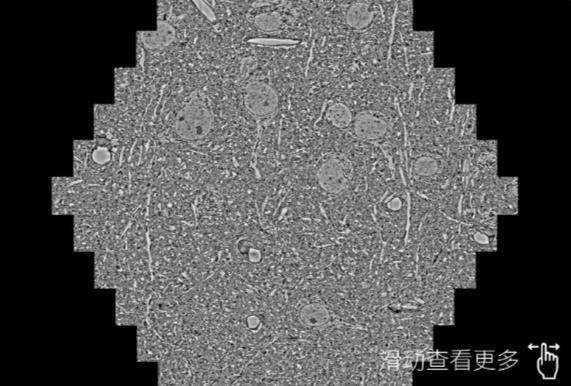

鼠脑切片。左图使用湖南蔡司湖南扫描电镜MultiSEM706对165μmx143pm面积区域成像,耗时仅需1.5秒。右图为鼠脑切片中30μm区域放大效果。样品由芝加哥大学B.Kasthuri提供。

使用蔡司高速湖南扫描电镜MultiSEM对1mm²人脑皮层组织进行高分辨成像,并对其中的各种细胞结构进行三维重构分析。左图展示了2x3mm²组织平面中锥体神经元的三维重构效果。右图显示了局部体积神经元三维重构。图像由哈佛大学chtman实验室提供,渲染图由D. Berger 制作。